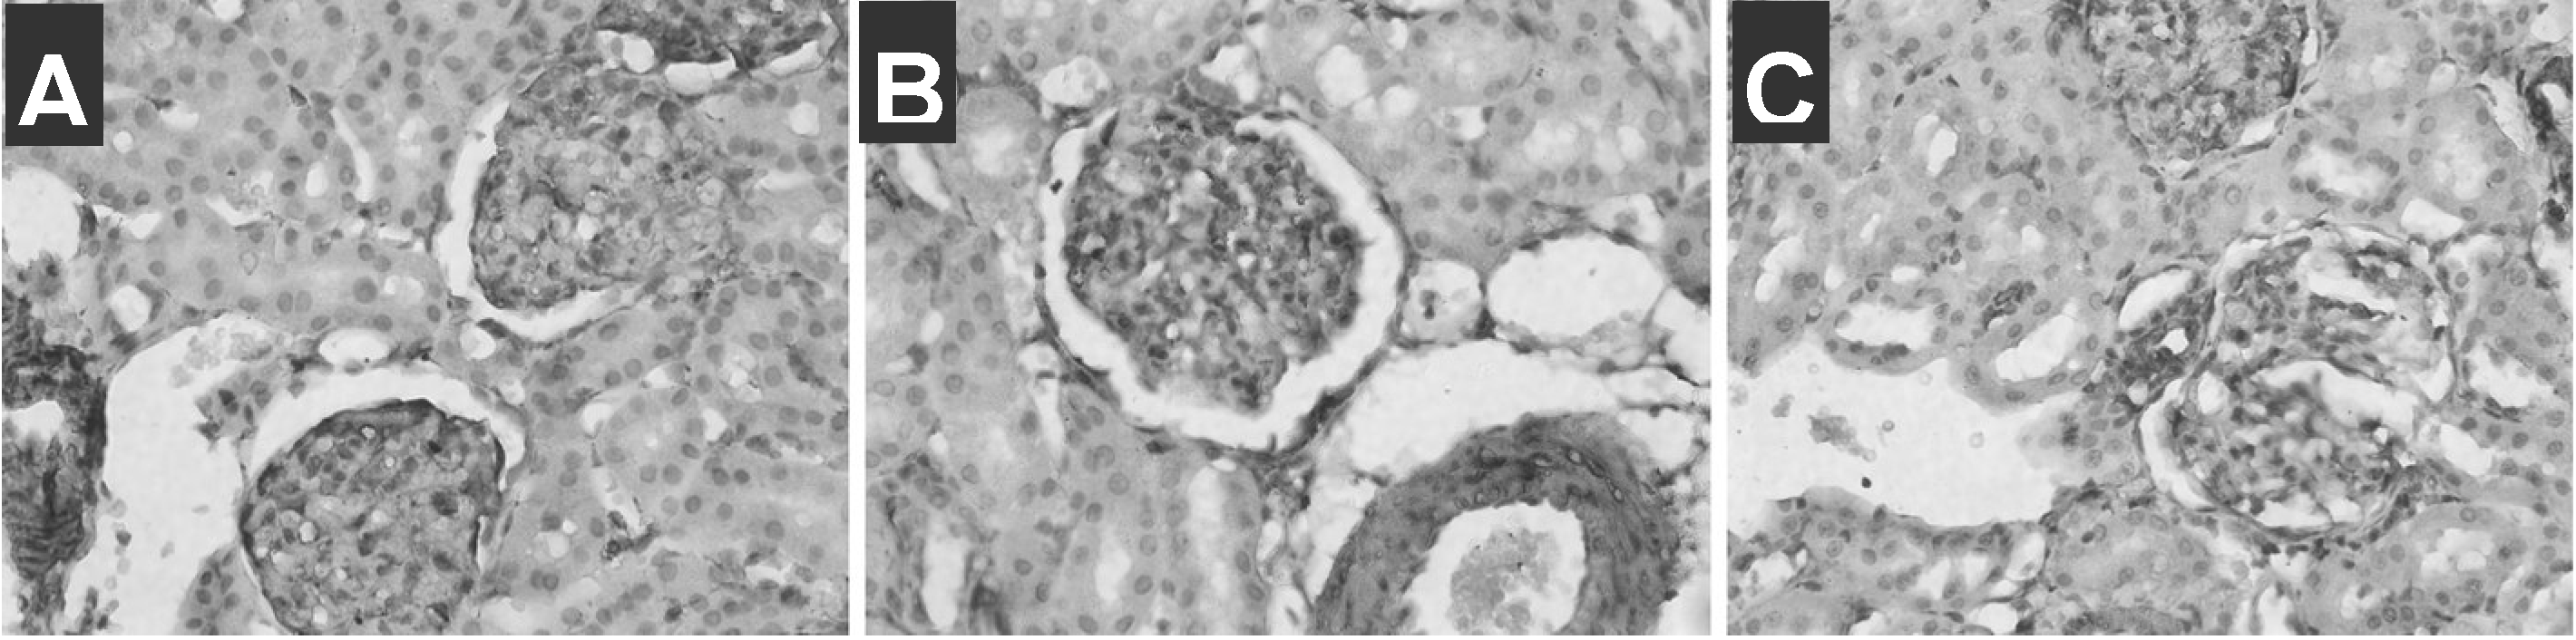

3.4 Immunohistochemistry examination

| Group | n | MLCK(absorbance) |

|---|---|---|

| Negative control | 6 | 13±7 |

| Control | 6 | 83±7 ** |

| Diabetic | 6 | 120±28 ** |

| Diabetic+ Insulin | 6 | 58±9 ** ▲ |